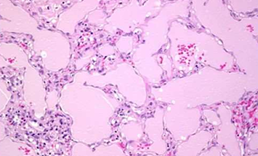

Fibrinous pericarditis

i. Pericardial surface contains pink fibrinous exudate.

ii. pericardium shows congestion and an acute inflammatory infiltrate composed predominantly of neutrophils.

(MICROSCOPIC APPEARANCE)